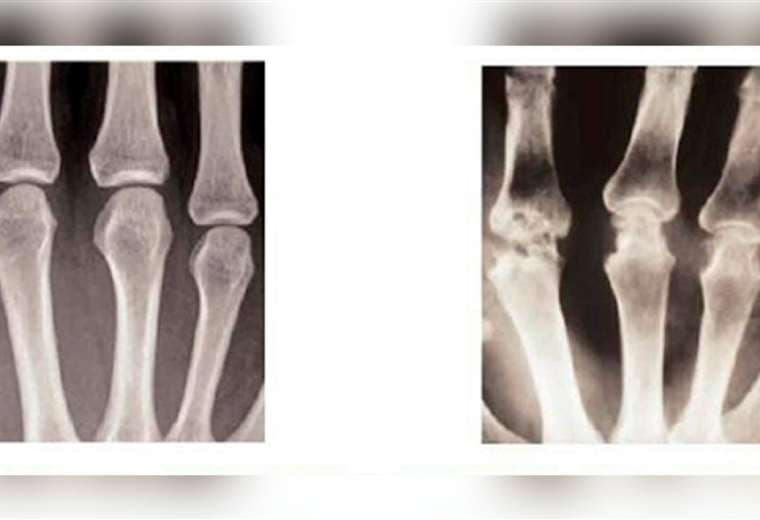

Día Mundial de la Artritis: todo lo que tiene que saber sobre esta enfermedad crónica

Hablamos sobre los síntomas de la artritis, su abordaje terapéutico y la rehabilitación de los pacientes.